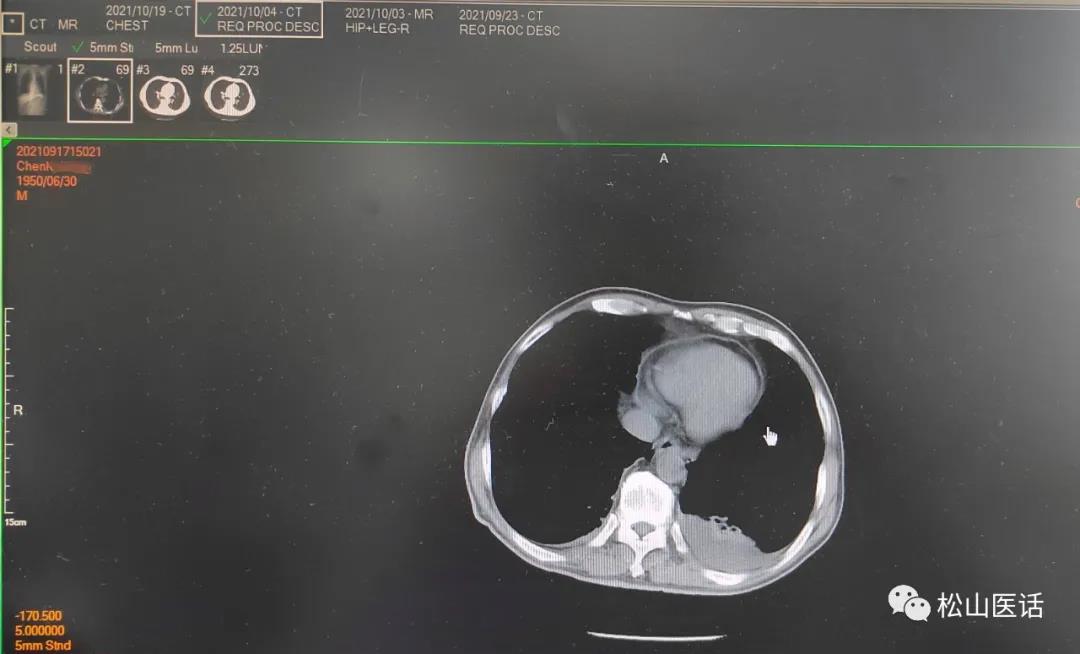

于是在10月4号复查了肺部CT以明确肺部感染的可能性,因为之前的肺部感染CT影像并不典型也不明显,只是报告有少量的胸腔积液。

2021-10-04CT报告

难道是肺部感染加重了?肺部CT的复查结果显示:

10月4号与9月23号比较没有明显改善,双侧胸腔少量积液但以左侧较多。

于是作出判断:骨髓的阳性细菌感染是正确的, 引起感染性高热可能性来自于肺部的胸腔少量积液,最大可能性是肺部真菌感染 ,